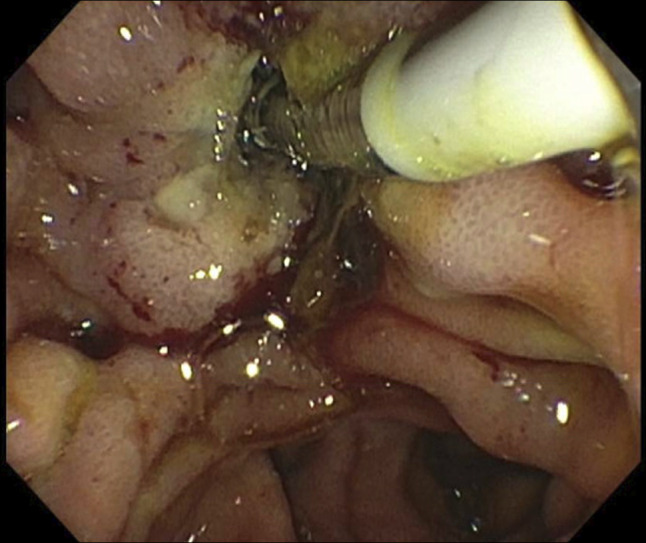

胆道射频消融是一种新兴的辅助和姑息性治疗壶腹和胆道肿瘤的患者。鉴于这些恶性肿瘤的高死亡率,有关长期并发症的数据有限。我们报告一个独特的病例括约肌切开术再狭窄导致胆道梗阻,在一个98岁的妇女壶腹腺癌的历史,治疗乳头切除和胆道射频消融(RFA)。内镜逆行胆管造影显示括约肌切开术部位再狭窄,通过重复括约肌切开术和支架置入术成功处理。本病例强调括约肌切开术再狭窄是胆道RFA的潜在晚期并发症,并强调RFA后患者需要意识到延迟性胆道梗阻。

Biliary radiofrequency ablation is an emerging adjunctive and palliative therapy for patients with ampullary and biliary tumors. Given the high mortality for these malignancies, data on long-term complications are limited. We report a unique case of sphincterotomy restenosis causing biliary obstruction in a 98-year-old woman with a history of ampullary adenocarcinoma treated with papillectomy and biliary radiofrequency ablation (RFA). Endoscopic retrograde cholangiopancreatography revealed restenosis at the sphincterotomy site, managed successfully with repeat sphincterotomy and stenting. This case highlights sphincterotomy restenosis as a potential late complication of biliary RFA and emphasizes the need for awareness of delayed biliary obstruction in post-RFA patients.